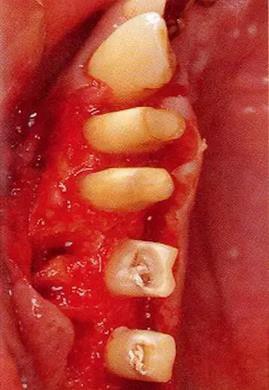

▼圖16-3

圖16-3 對(duì)右上6.7顎側(cè)根的頰側(cè)牙槽中間骨脊缺失進(jìn)行處理,對(duì)應(yīng)高度來對(duì)右上5遠(yuǎn)中牙槽骨進(jìn)行少量切除。之后,對(duì)應(yīng)右上5遠(yuǎn)中牙槽骨的高度對(duì)近中以及右上4的牙槽骨進(jìn)行治療處理。牙槽骨的整體形態(tài)盡可能平坦,沒有極端的段差留下。之后,通過apically positioned flap進(jìn)行縫合固定。結(jié)果就能提高術(shù)后清潔性,得到良好的牙周環(huán)境。